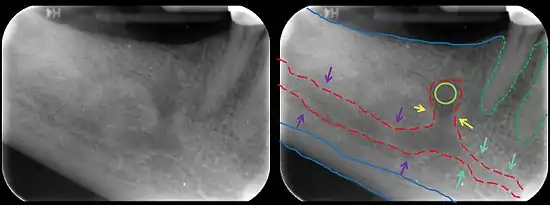

The mandibular canal is continuous with tow foramina: the mental foramen which opens in the mental region of the mandible and carried the distal fibres of the inferior alveolar nerve as the mental nerve; and the mandibular foramen on medial aspect of ramus, into which the mandibular nerve enters to become the inferior alveolar nerve. The mandibular canal often runs close to the apices of the third molar tooth, and the inferior alveolar nerve can become damaged during removal of this tooth, causing sensory disturbance in the distribution of the nerve. This is sometimes the case for the second or first molar teeth, and care must be taken during removal or root canal treatment in such cases to prevent nerve injury or extrusion of root canal filling materials.[2]

Variations

Several variations of the mandibular canal exist with varying frequency. The most common variant is the retromolar canal (~10 % of canals), whereby a branch is given off in the mandibular ramus which terminates in the retromolar region of the mandible. The retromolar canal may cause bleeding during surgery in the retromolar region such as removal of mandibular third molar teeth. Other variants include a bifid canal with a branch (~41%):[3] following the course of the main mandibular canal before re-joining it (forward or buccolingual type); terminating at the apex of a tooth, usually the molar teeth (dental type); opening as an accessory mental foramen.[4] A trifid mandibular canal variation has also been described.[5][6]